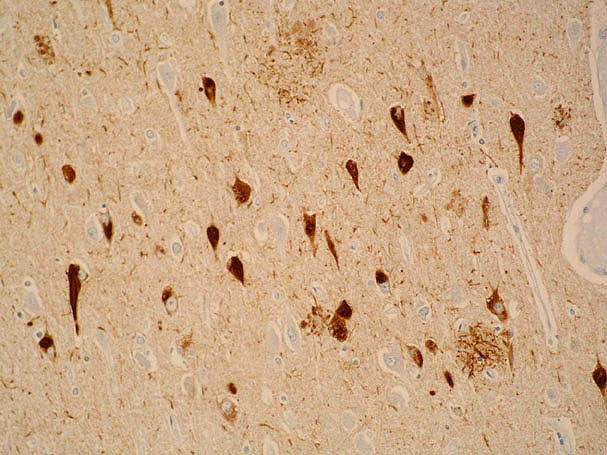

Alfa-sinucleína

Cuerpo de Lewy en sustancia negra